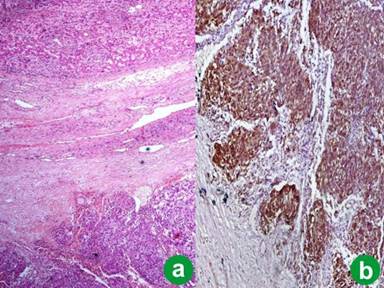

On the basis of tumor size and mitotic counts on histology and immunohistochemistry, the tumor was reported as a high-risk EGIST. The postoperative course was uneventful. After tumor resection, the patient was followed up for 6 months. Two years later, the patient presented with abdominal pain and loss of weight. CECT abdomen revealed a metastatic lesion in the right lobe of the liver, measuring 9x7 cm. Subsequently, a non anatomical resection of segments V, VI and VII of the liver was carried out. On histology, a metastatic GIST was diagnosed (Figure 2a). The morphology of the tumor resembled the primary tumor with similar mitotic counts and was positive for CD117 (Figure 2b). The patient was started on imatinib (400 mg bid). The patient has been followed regularly with improvement in symptoms. The last follow-up, two years after the detection of the metastasis, showed no recurrence or metastasis on radiology.

Figure 2. Metastatic tumor deposits in the liver parenchyma (H&E, x100) (a.) with strong CD117 expression (diaminobenzidine chromogen, x200) (b.) |